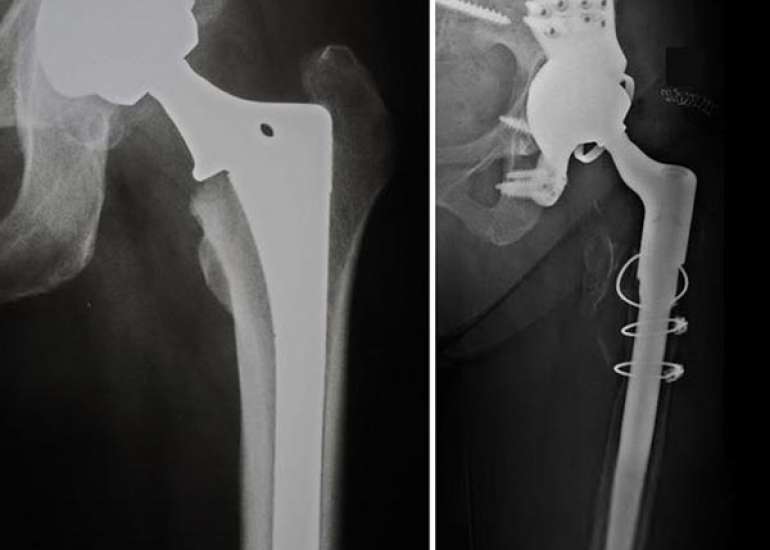

Dr Ramneek Mahajan is Obtained medical degree from Government Medical College, Aurangabad, Maharashtra in 1997 Completed a Post-Graduation from Government Medical College, Aurangabad in 2003 and his advanced training Orthopaedic Fellowship in Singapore, Germany & Australia. Worked extensively in Primary Hip, Knee and Revision Joint Replacement. Took up the public position as Head of Orthopaedics at the Nova Specialty Hospital, Kailash Colony from 2010 to 2014. Visiting Orthopaedic Surgeon in the Fortis Hospital from 2009 to 2014.